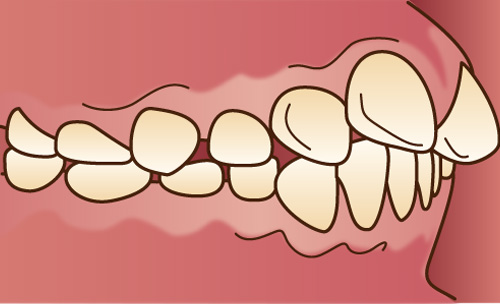

上顎の前歯が前に傾斜していたり、突き出ていたりする状態で、一般的に「出っ歯」と呼ばれています。

下顎が上顎よりも前に突き出ている状態で、横顔がしゃくれたように見えます。かみ合わせが反対になるので「反対咬合」、あるいは「受け口」とも呼ばれています。